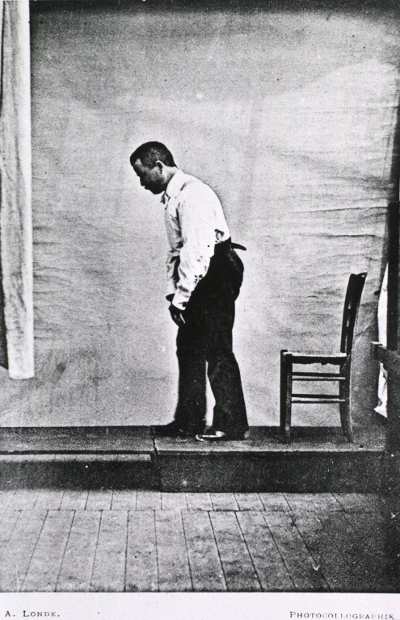

1969年2月13日

尽管帕金森病早在1817年就有报道,那时候被称作是"震颤麻痹",但是一个多世纪过去了,还没有有效地治疗方法。到了1950年代,终于出现了转机。研究者发现帕金森病患者的脑中多巴胺的含量偏低。这篇文章发现了一个叫做左旋多巴的多巴胺的前体物质可以部分控制患者的帕金森病症状。后来又加入了卡比多巴以缓和左旋多巴的副作用。两者的联合尽管还不完美,但却成为了如今多帕金森病治疗的基石。